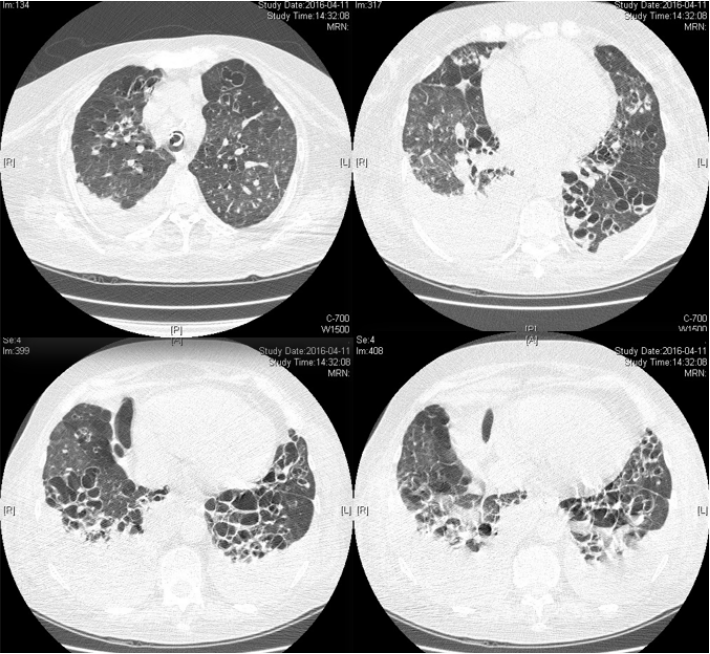

患者53岁男性,因“喘憋2天、加重1天”于2021年2月11日入院。

病史:入院2天前醉酒后意识障碍,后恢复意识后出现高热(体温39.2℃),急诊期间出现呼吸困难进行性加重,因氧合不能维持予气管插管,后收住RICU。

既往史:乙型肝炎10年,高血压5年。

体格检查:T 39℃,P 145次/分,R 28次/分,BP 73/47 mmHg(去甲肾上腺素18 μg/min);镇静状态,四肢末梢花斑;双肺呼吸音粗,可闻及湿啰音,右肺呼吸音减低;腹软,肝脾肋下未及,移动性浊音阴性,双下肢无水肿。2月11日胸部CT见图1。

图片

图1  病例1入院胸部CT

建立ECMO前,患者血流动力学不稳定,氧合较差,P/F 55 mmHg(P-A/C:Pi 10 cmH2O,PEEP 14 cmH2O,FiO2 1.0),感染指标异常升高。呼吸力学:Crs 35 ml/cmH2O,R 16 cmH2O/(L·S)。建立ECMO后完善病原学检查,并予抗感染治疗(表1)